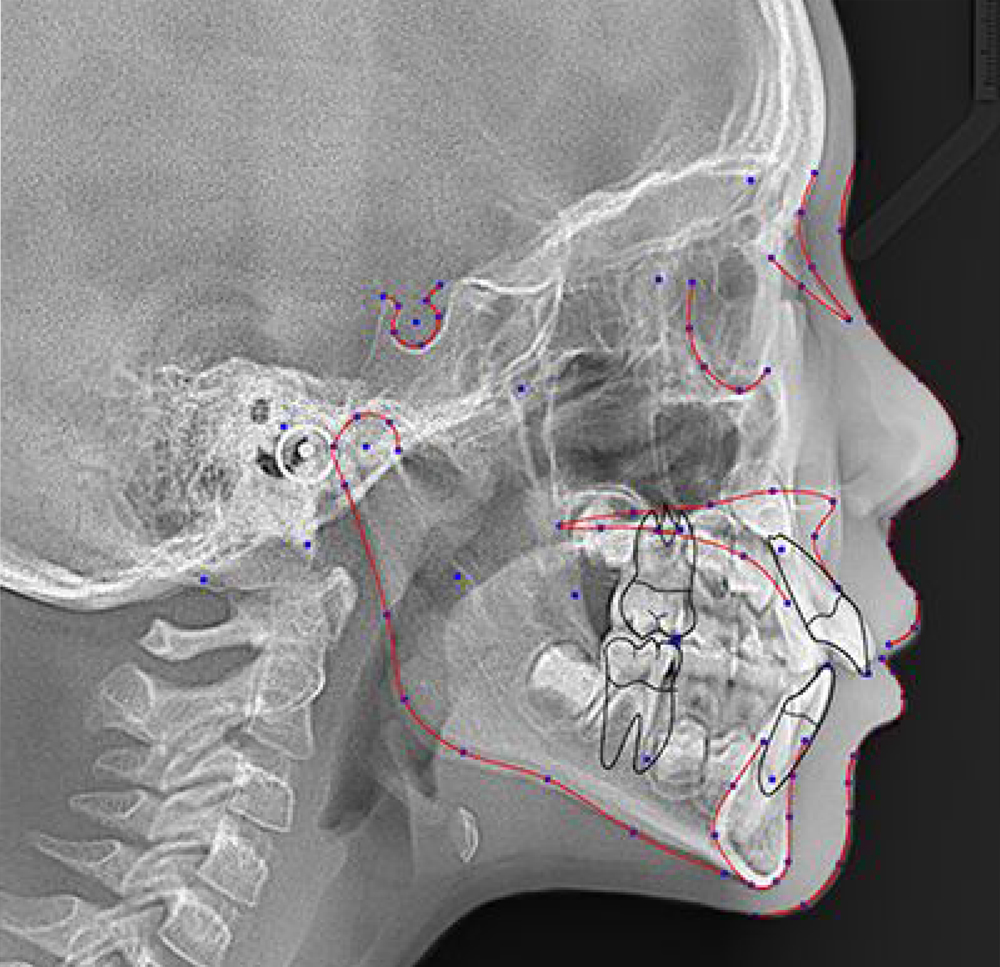

Today’s digital imaging software provides tools that allow for 1:1 measurement of ceph X-rays, which is a concern for many dental professionals migrating from analogue systems. In addition, modern imaging software allows you to create serial superimpositions with cephalometric tracing. The ability to compare and contrast those images can be one of the most effective ways to measure growth, and these images can also help you see how the mouth is responding to treatments such as orthodontics. Plus, advanced treatment simulation modules available in some software packages, allow you to diagnose, plan, and present cases using 2D digital ceph X-rays, improving case acceptance.